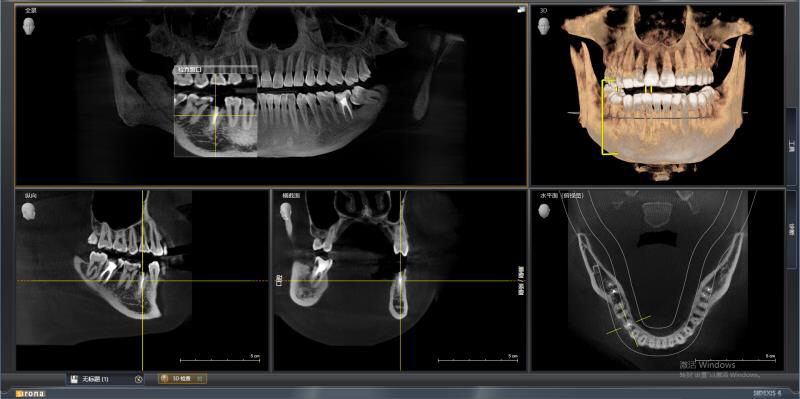

今天老卢给大家分享一例后牙单颗即拔即种的种植病例。

患者是一位刚参加工作的23岁小伙子,右下5号牙由于根管治疗后只是简单补上,没有做高嵌体、全瓷冠等修复方式把牙齿保护起来,吃硬物咬碎且未及时就医,长期腐蚀导致成无法修复的残根,老卢没有采用传统的牙冠桥体修复方式,因为那样对患牙两边的邻牙损伤较大,而是采用老卢最擅长的种植修复,当然老卢做为一名从业20多年的全科医生,其他治疗技术也是不弱的,欢迎牙齿不好的朋友们前来体验。

回到主题,老卢为这位小伙子采用即拔即种的方式,由于骨量条件尚可,植体植入后直接上愈合基台,这样就可以让患者提前了戴牙时间,早一些用上这颗牙齿吃东西。希望小伙子能体会老卢的良苦用心,以后好好保护自己的牙齿。